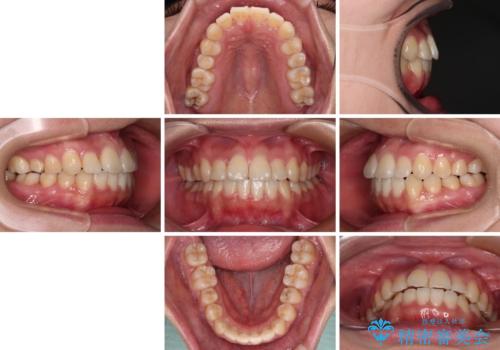

反対咬合とクロスバイトを改善して噛みやすい咬合に

- 前歯のデコボコとクロスバイトを気にして来院された患者様です。

骨格的に下顎が前方位の受け口傾向であり、それが原因でクロスバイトとなっていました。

右奥の歯が180度回転していることで、噛む度にワイヤーに無理な力がかかったようで、頻繁にワイヤーが切れてしまいました。また、下顎を後方に移動させるためのアンカースクリューも脱離することが多く、治療期間が長くなってしまいました。